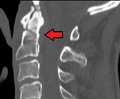

Type 2 dens fracture

- Type II Fracture - Extends through the base of the dens. It is the most commonly encountered fracture for this region of the axis. This type is unstable and has a high rate of non-union.